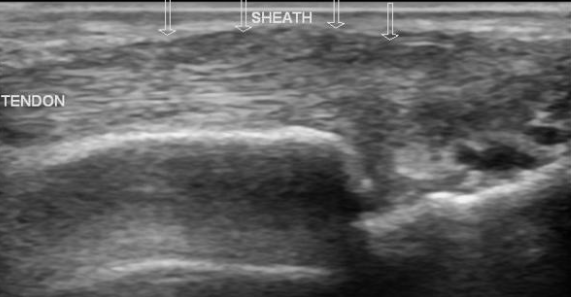

Tenosynovite de la jeune maman (de Quervain)

- Ténosynovite du premier compartiment

- Inflammation des tendons au niveau de la styloide radiale